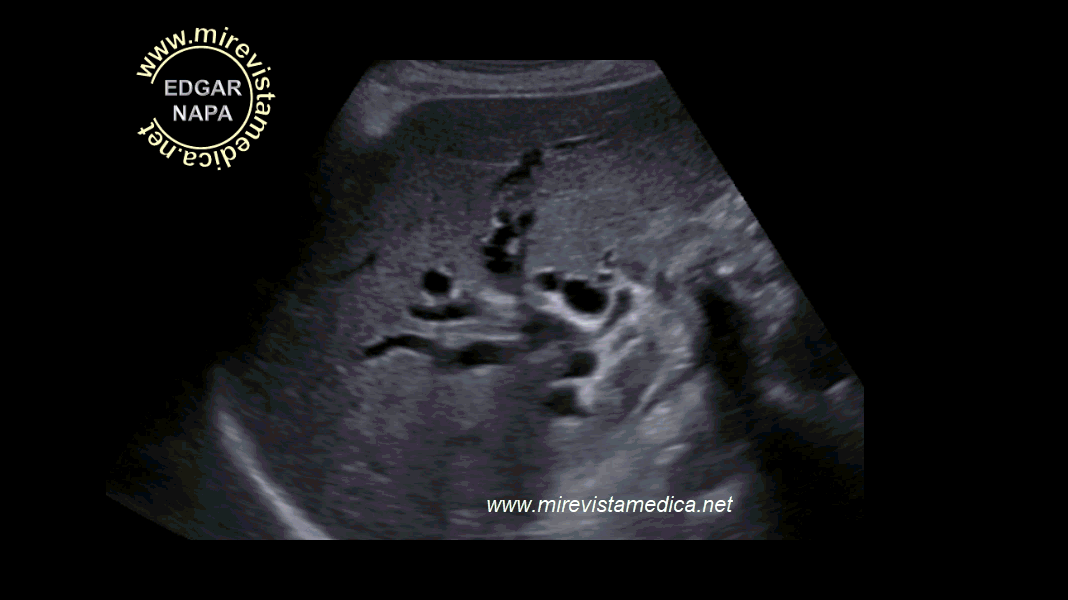

Anatomía imagenológica de la vía biliar